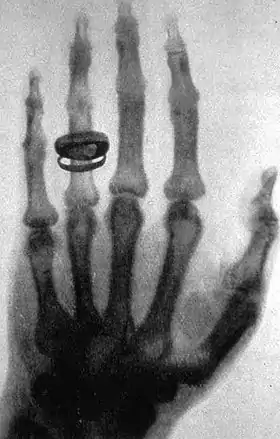

پرتو X، پرتوی با طول موج بسیار کوتاه و قابلیت نفوذ بسیار زیاد است، و از بیشتر مواد میگذرد. فیزیکدانان برای آنالیز مواد بلوری، بسیار از این پرتو بهره بردهاند، و در پزشکی نیز به نامهای رادیوگرافی و رادیولوژی بهکار میرود.

در هشتم نوامبر ۱۸۹۵، رونتگن، سرگرم کار روی پرتو کاتدی با لوله کروکس-هیتورف (لامپ کروکس) بود. این لوله که در آن زمان بارها از سوی فیزیکدانان استفاده میشد، حباب شیشهای داشت که هوای آن تقریباً تخلیه شده، دو الکترود به فاصله چند سانتیمتر از هم در آن قرار داشتند. با برقراری اختلاف پتانسیل زیاد، در حدود چندین هزار ولت، بین الکترودها، پرتو کاتدی (الکترونها) از کاتد (الکترود منفی) به آند (الکترود مثبت) میرفتند، به عبارت دیگر، به مسیر خود ادامه میدادند تا به دیوارهٔ شیشه لوله برخورند. رونتگن در صفحه کاغذ آغشته به کریستالهای پلاتین، سیانور و باریم که در کنار لوله کروکس-هیتورف قرار داشت فلورسانس درخشانی دید. وی پرتوی را که بسیار پرنفوذتر از پرتو کاتدی بود، کشف کرد. سپس رونتگن مشتاقانه در چند هفته با پیگیری این ایده و با تجربهٔ دقیق، به بررسی ویژگیهای این پرتو، که آن را پرتو ایکس نامید، پرداخت. کشف پرتو ایکس و کاربرد وسیع آن در تصویربرداری پزشکی، به نجات انسانهای زیادی انجامید، بهگونهای که تصور علم پزشکی بدون تصویربرداری پرتو ایکس، سخت است.